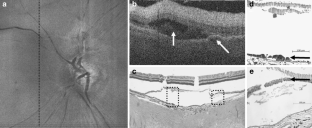

AMD pathology was detected and localized in four eyes by SDOCT. The SDOCT images correlated with the histopathology observed by light microscopy in each sectioned eye. Pathologies included a subfoveal neovascular lesion with subretinal fluid, peripapillary neovascularization, epiretinal membrane, foveal cyst, choroidal folds, and drusen. Similar imaging was possible with the simplified setup.

Fig. 2